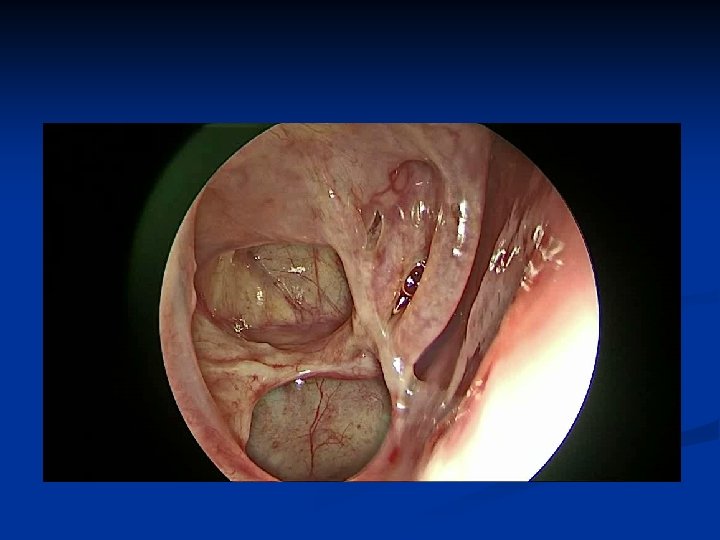

Kazuistika č. 1 n n n 67 ročná pacientka Infekt HCD v 02/2015, odvtedy výtok čírej tekutiny z pr. nosnej dierky, bolesť hlavy 29. 7. 2015 prvé vyš. na našej ORL amb. Vyš. β 2 TRF – potvrdenie likvoru CT PND Suponovaná idiopatická rinolikvorea vpravo, indik. FESS operácia na 21. 9. 2015

Histológia Makroopis : Zaslaný fragmentovaný materiál o spoločnej veľkosti cca 10 x 8 x 5 mm, béžovej farby, mäkkoelastickej konzistencie, nerovného, lesklého vzhľadu. Záver : V kompletne vyšetrenom materiáli ide o - mozgové tkanivo s miernym až stredne ťažkým edémom - bez malígnych nádorových zmien - bez známok zápalu - taktiež zachytené mikrofragmenty respiračnej sliznice bez známok zápalu - mozgové tkanivo je prítomné v cca 95% objemu zaslaného materiálu

Po operácii n Indik. MRI vyš. vzhľadom k histolog. nálezu – mozgové tkanivo n 10 dní po operácii pretrváva sekrécia z pr. nos. dierky, hojenie primerané n 21 dní od operácie výtok z nosa ustal n Očné a neurolog. vyš. negat. n Pri ďalších kontrolách subj. bez ťažkostí, endosk. nález zhojený